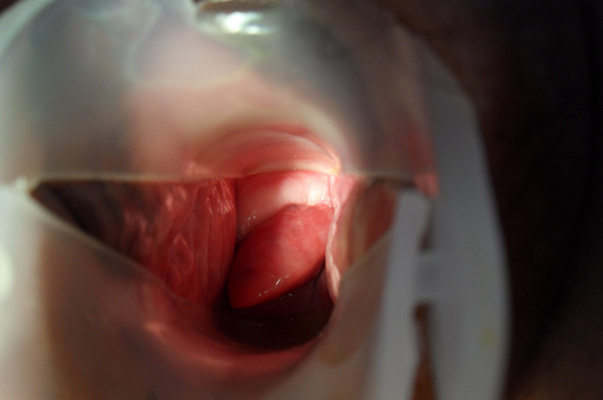

子宮頸糜爛圖片

宮頸糜爛 (8)

宮頸糜爛 (9)

宮頸糜爛 (56)

宮頸糜爛 (57)

宮頸糜爛 (58)

宮頸糜爛 (59)

宮頸糜爛 (6)

宮頸糜爛 (60)

宮頸糜爛 (7)

宮頸糜爛 (40)

宮頸糜爛 (41)

宮頸糜爛 (42)

宮頸糜爛 (43)

宮頸糜爛 (44)

宮頸糜爛 (45)

宮頸糜爛 (46)

宮頸糜爛 (47)

宮頸糜爛 (48)

宮頸糜爛 (49)

宮頸糜爛 (5)